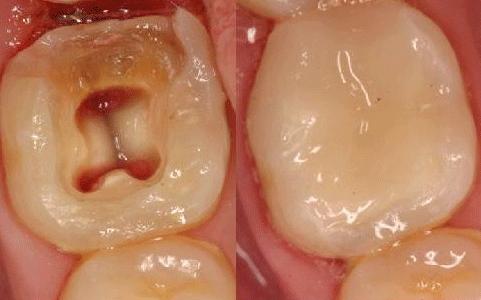

Trám răng sâu giá bao nhiêu là hợp lý?

Câu hỏi: Chào bác sĩ. Răng em bị sâu cũng đã lâu, chỗ răng đau có nhiều vết đen to và lấy tay ấn thì rất đau. Em đã cố…